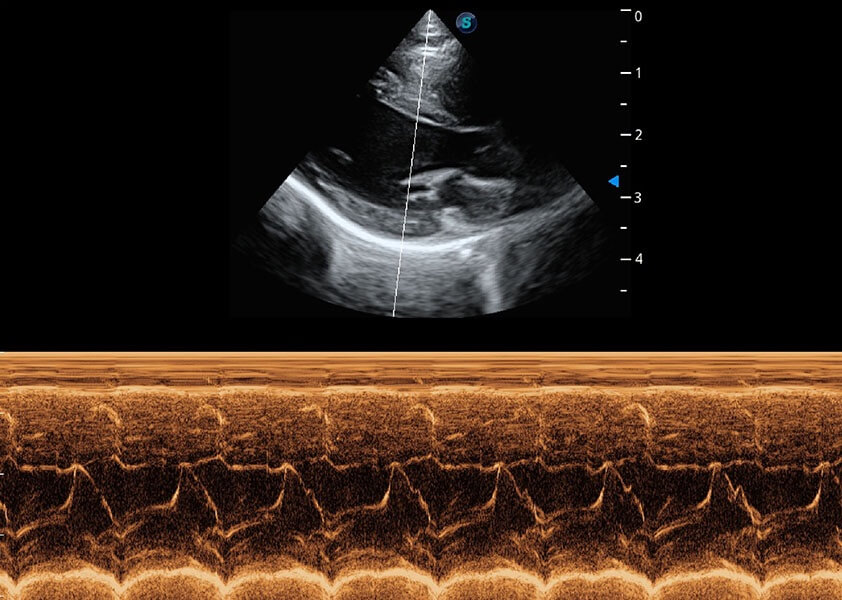

ProPet 60 作为一款高端台式动物超声设备,为动物医生的日常诊断提供了一系列贴合动物临床需求、解决临床实际问题的高级成像功能。凭借全系列高清探头,满足医生对腹部、心脏、生殖、浅表、肌骨等成像的所有需求,切实帮助您提升检查效率,提高诊断信心。

动物是人类最亲密的朋友和最值得信赖的伙伴。米兰官方网站也一直致力于探索动物专用的超声影像解决方案。 全新推出的ProPet系列,是米兰官方网站在动物超声影像智能化、专业化、精准化的一次跨越式革新。动物不能用言语来表述自己的不适,通过超声影像,ProPet系列搭建了动物医生与不同物种沟通的“桥梁”,为动物医生注入了“治愈之力”。